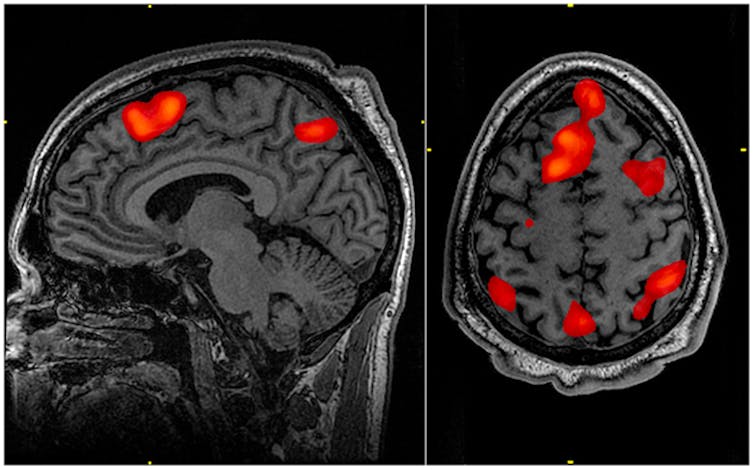

The reason this approach has been so popular is partly due to technologies which are giving us unprecedented insight into the brain. Functional magnetic resonance imaging (fMRI), which tracks changes in blood flow in the brain, allows scientists to see brain areas light up in response to activities – helping them map functions. Meanwhile, Optogenetics, a technique that uses genetic modification of neurons so that their electrical activity can be controlled with light pulses – can help us to explore their specific contribution to brain function.

The problem can be illustrated by a recent study which found that the psychedelic drug LSD can disrupt the modular organisation that can explain vision. What’s more, the level of disorganisation is linked with the severity of the the “breakdown of the self” that people commonly experience when taking the drug. The study found that the drug affected the way that several brain regions were communicating with the rest of the brain, increasing their level of connectivity. So if we ever want to understand what our sense of self really is, we need to understand the underlying connectivity between brain regions as part of a complex network.

So the way forward for neuroscience may be to focus more on general neural recordings (with optogenetics or fMRI) – without aiming to hold each neuron or brain region responsible for any particular function. This could be fed into theoretical network research, which has the potential to account for a variety of observations and provide an integrated functional explanation. In fact, such a theory should help us design experiments, rather than only the other way around.